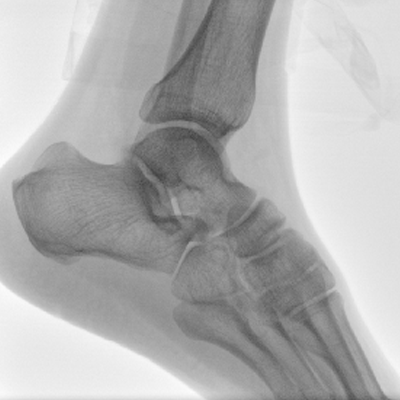

Clinical picture

臨床圖片